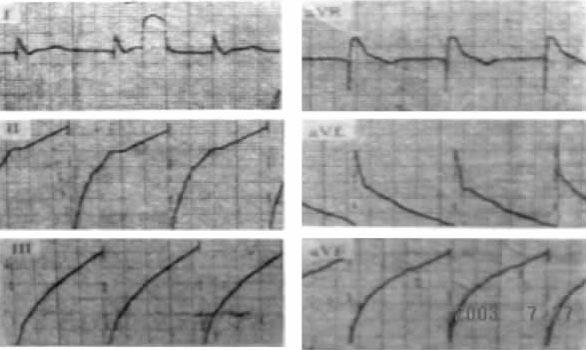

刺激信号代表脉冲发生器释出的脉冲电流,又称起搏信号或脉冲信号。体表心电图上的刺激信号表现为自基线上发生的一个陡直的电位偏转。刺激信号的时限很短而振幅差别很大。目前常用的脉冲发生器发放的脉冲刺激时限(脉宽)多在0.42ms左右,当以25mm/s的走纸速度记录体表心电图时,这个刺激信号表现为基线上的一条垂直线,故又被称为“钉样信号”。刺激信号的振幅与导线上两个电极之间的距离呈正比关系。因此,在单极起搏时,两个电极间相距较远,刺激信号常常较大,有时呈双相波形(可能由于较大的刺激信号回到等电位线时的“过冲现象”所致,图7-1-1)。而在双极起搏时,由于起搏电极间距近,刺激信号相对较小,某些导联体表心电图上甚至看不见。

图7-1-1 单极性起搏心电图:由于刺激信号过大,且发生过冲现象,使QRS波明显增宽变形

需要注意的是刺激振幅较大的起搏信号,其后的电位衰减指数曲线亦较大,两者可貌似正常的QRS波形。故此时应根据T波有无来判定是否存在真正的心室除极还是起搏脱漏(刺激信号后无心室除极波)。另需注意的是心电图上观察到的刺激信号方向,系由脉冲刺激的向量(自负极至正极)与心电图导联之间的关系所决定,故实际取决于埋藏式脉冲发生器在体内的位置。因此,不能以刺激信号的方向来判断起搏部位,而应通过观察起搏搏动的QRS波群形态和空间方位作出正确的定位和判断。